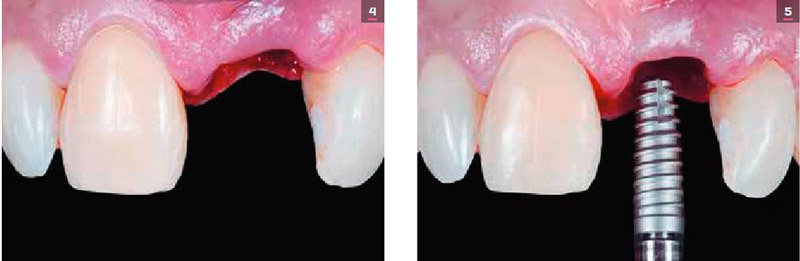

No caso clínico apresentado, a paciente foi tratada com um implante que substituiu o incisivo central superior esquerdo (elemento 21). O pilar protético sobre o implante foi confeccionado por meio da tecnologia CAD/CAM em zircônia, posteriormente recoberta com cerâmica feldspática, simulando o substrato do incisivo superior direito (elemento 11), no qual planejou-se uma faceta cerâmica – pela queixa da paciente em relação ao seu escurecimento. Este procedimento permitiu ao técnico a confecção de duas facetas, uniformizando o uso dos materiais cerâmicos.